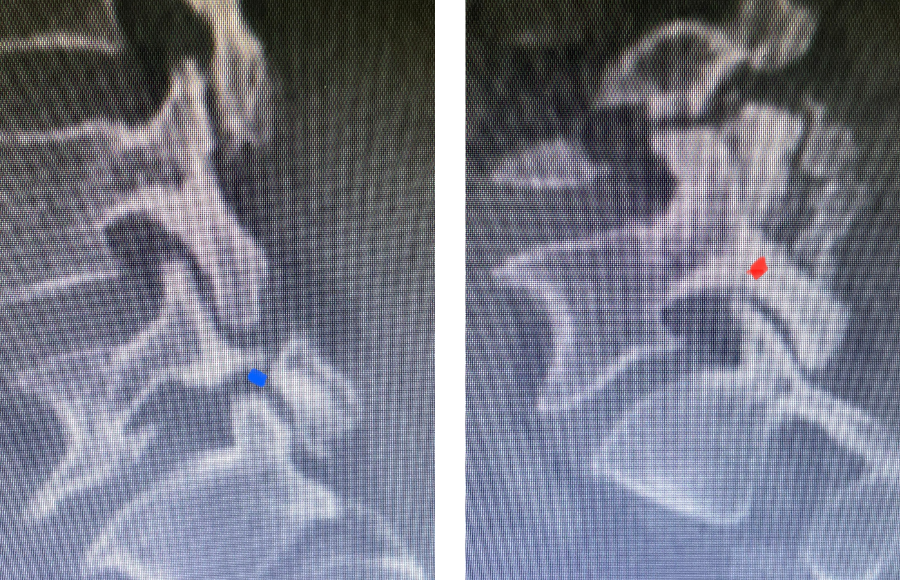

Revision surgery is more involved than primary surgery. In order to start decompressing this large complex, you must develop a plane; you have to find the edge of sometimes a remnant of a lamina or the lamina that can be buried in scar. You must carefully dissect the edge with a sharp upbiting curette and then either using a sharp Leksell to start removing this lamina or use a fine Kerrison to widen the plane and exposure and begin to expose the normal ligamentum above. In this case it was critical to expose and decompress the L3 nerve roots bilaterally. What is quite helpful is finding the inferior edge of the L2 facets. Then one must lift up the inferior L2 process up with a curette and simultaneously insert a Kerrison into joint space and remove the whole facet process. This is a great move because it allows access to the plane between the superior facet and the descending nerve root and a starting point to fully decompress the nerve root. Because of scarring there often is not a clear plane in order to accomplish the decompression. Care is taken to make sure there is a clear separation between edge of bone and dura during the process of inserting a Kerrison edge. The important part of this is feeling your opening and actually using your Kerrison as a dissecting tool once an edge has been established to perform a foraminotomy. We were able to remove the inferior L2 facet process with impunity as we knew we were performing an instrumented fusion to L2. The patient’s had a prior L3-5 instrumented fusion which upon exploration was solidly fused. It was decided to remove her prior hardware as it served its purpose and add a short segment from L2-3 (Fig 5). Patient did well after her surgery with relief of her right leg pain.

Fig 5: intraoperative fluoroscopic images demonstrating L2-3 screw placement.